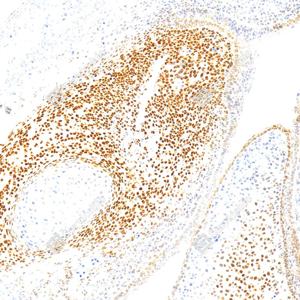

IHC检测RUNX2蛋白(货号 GB125631). 样品: 人食管癌, 4%多聚甲醛 (货号G1101) 固定12-24小时. 抗原修复: 柠檬酸抗原修复液(干粉, pH 6.0) (G1201), 高压锅均匀喷气计时2分钟. —抗: 1: 500稀释, 4℃ 孵育过夜. 二抗: S-vision免疫组化多聚二抗(山羊抗小鼠), 即用型(货号G1301), 室温孵育20分钟. |